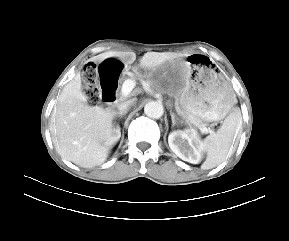

标题: CT19533:病变来源于哪?

患者,男,发现上腹部包块两月余。

病变位于肝胃间隙,实际就是位于小网膜囊(左肝下后间隙),呈轻度不均匀性强化,腹腔内及腹膜后见多发肿大淋巴结。所以我考虑肝胃间隙恶性胃肠间质瘤并淋巴结转移。

病灶强化不显著,灶周及腹膜后见多量淋巴结肿大,考虑淋巴瘤可能,其次考虑间质瘤

病灶与胰腺分界不清,来源于胰腺?

强化后病变与胃壁分界清楚,并且血供不是来源胃壁血管。考虑胰腺颈体癌并腹腔腹膜后淋巴结转移。